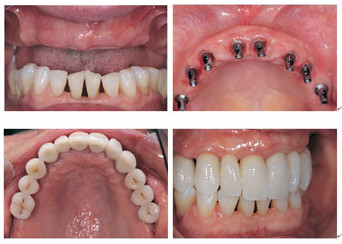

杭州牙科医院新引进的即刻种植技术,利用3~4毫米的小切口,将人工牙根“种”入口腔内,摆脱了传统种植牙切开翻起牙肉、缝合、拆线等步骤,将创伤降低到最小程度,大大减少了肿痛和出血量。具有数字化精准预测定位、10分钟种植、堪比真牙、使用寿命长等特点,势必成为种植牙技术的新风向标。

擅长:种植牙历史超过二十年,种植牙数量超万颗。